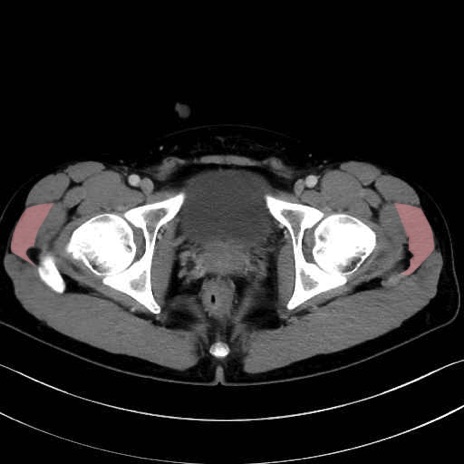

中殿筋 (Gluteus medius)